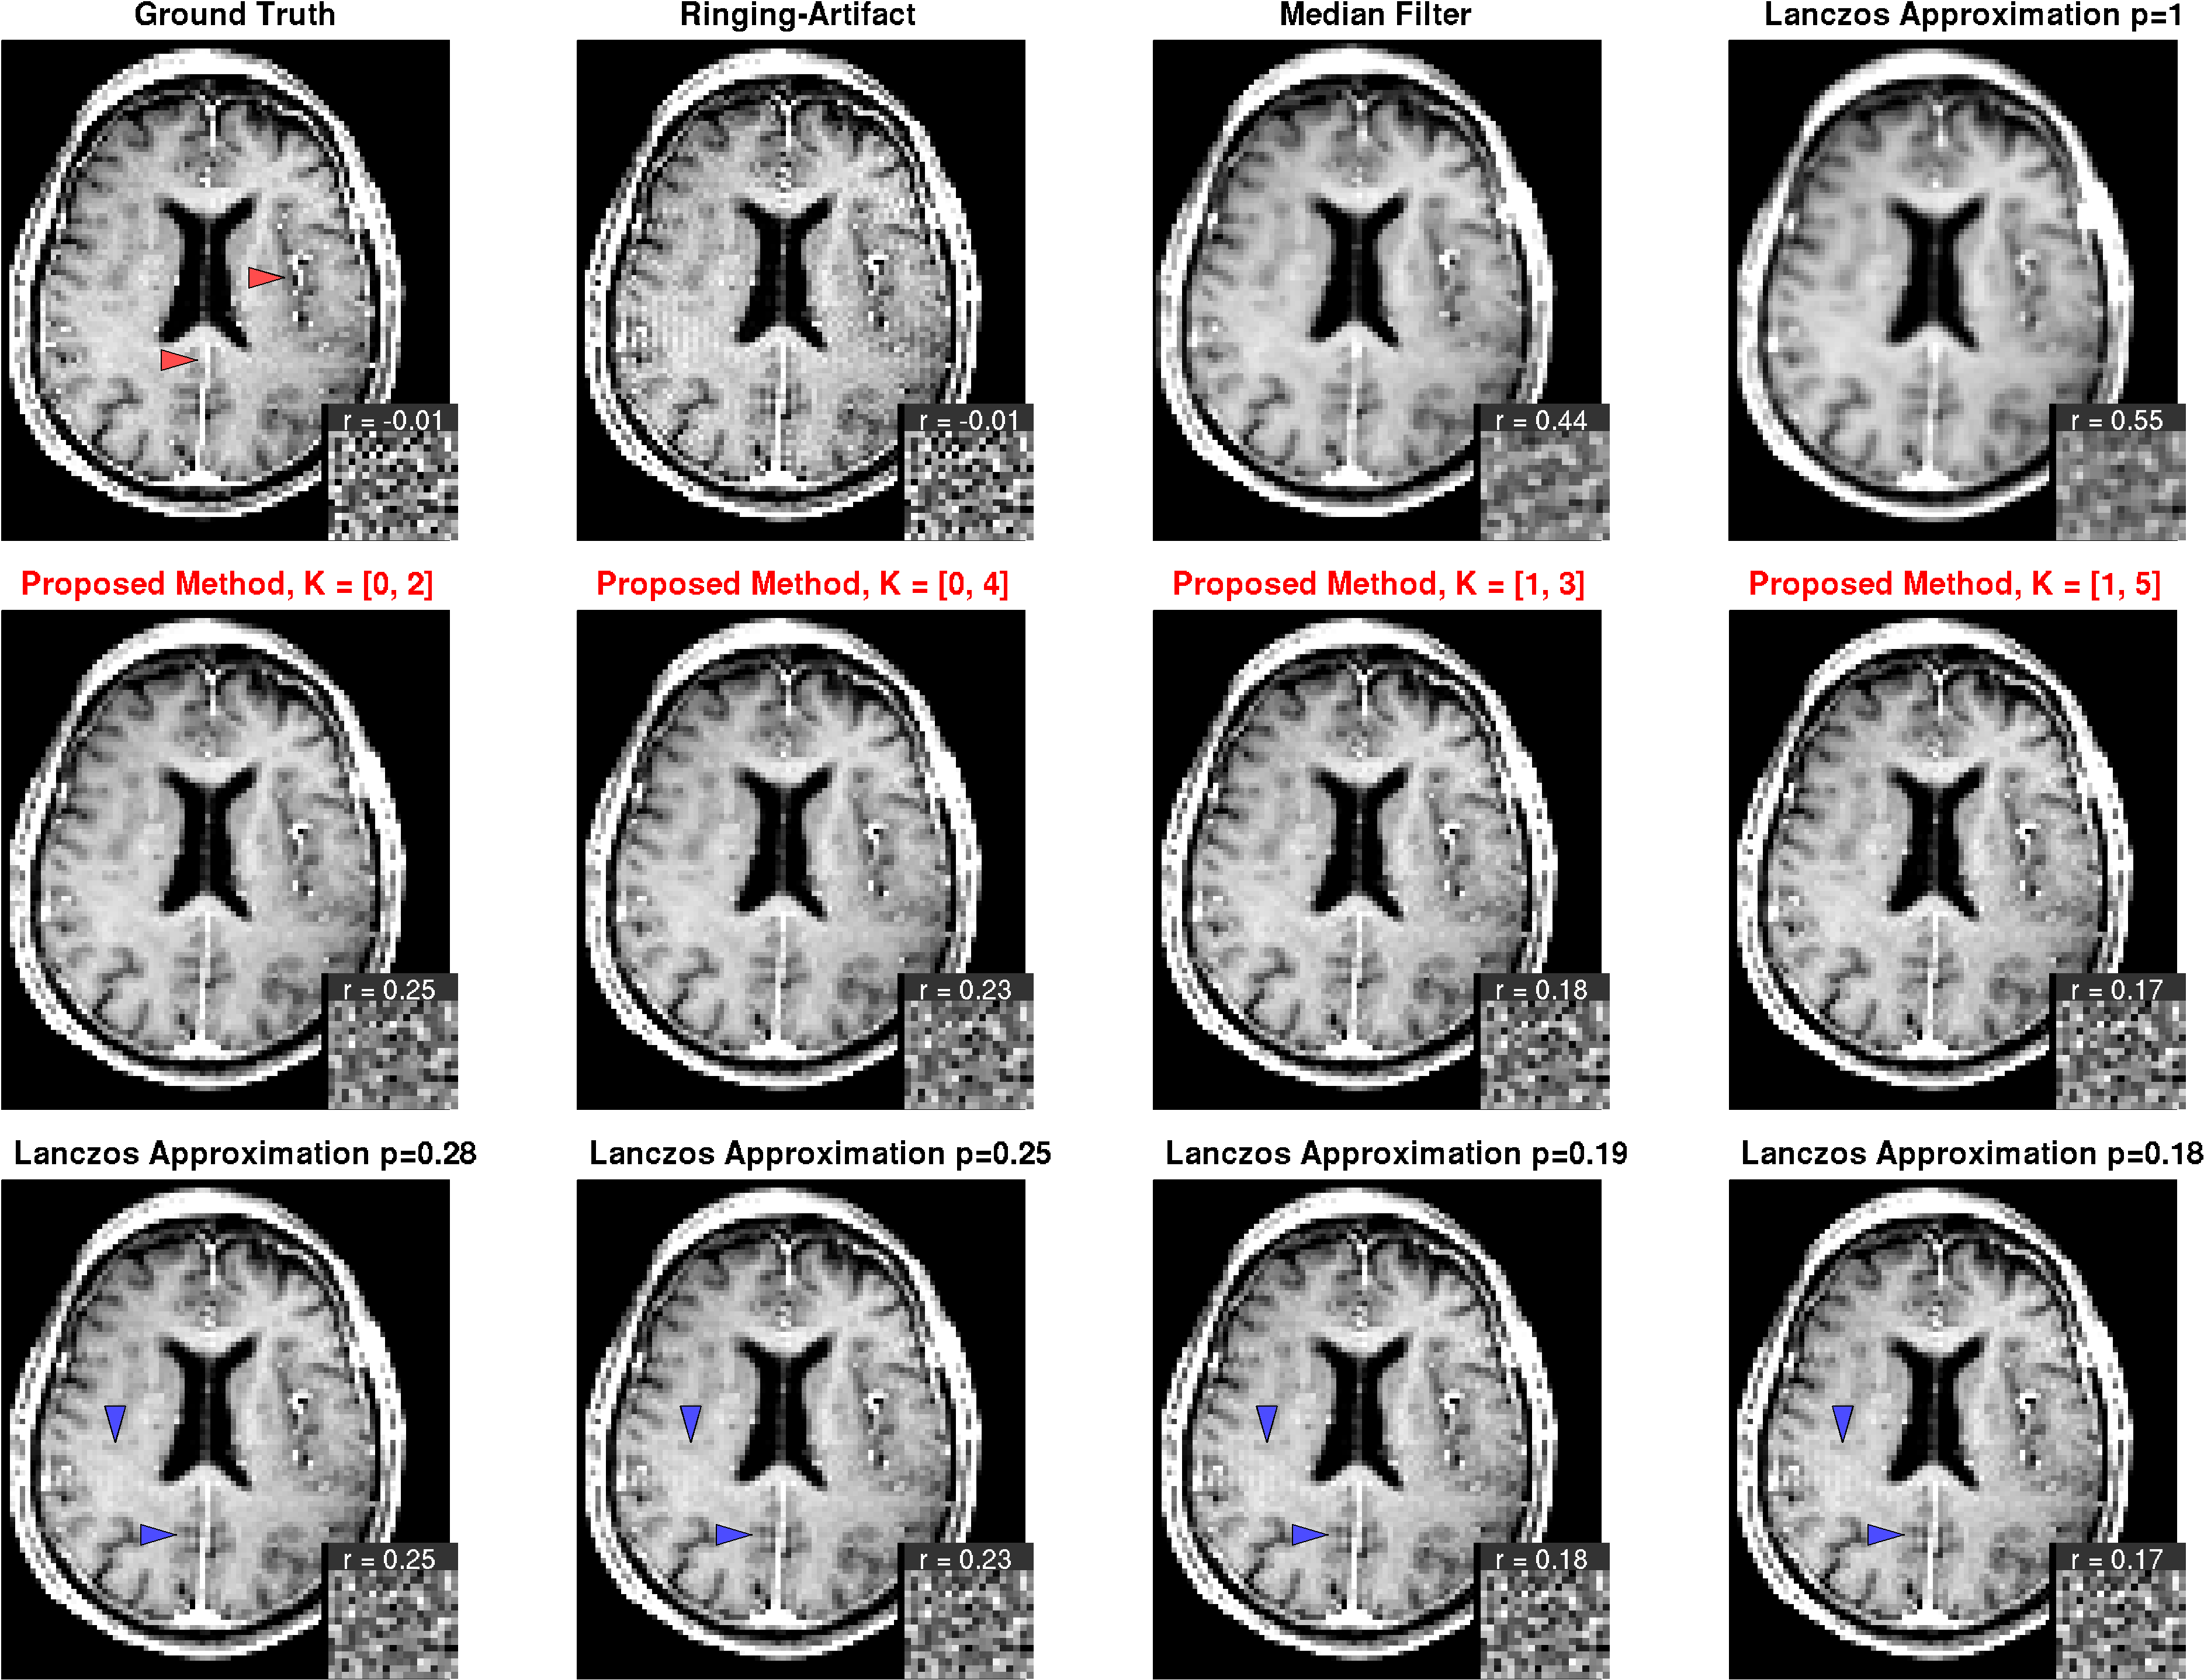

Numerical Phantoms

The method was applied to two numerical phantoms (Fig. 4). For the first phantom, a polygonal shape with some stripes and small structures was simulated. Starting with a high-resolution image, the artifact was simulated by reconstructing the image from a truncated k-space with a reduction factor of 20. Second, for a more realistic brain phantom, data from a -weighted post-contrast MRI measurement of the brain was used. The artifact was artificially enhanced by re-reconstructing the image from a smaller k-space with a reduction factor of 4. In both cases, a ‘ground truth’ image without artifact, but with the same decreased spatial resolution was generated by convolving the high-resolution image with a boxcar function, and sampling the result on the corresponding low-resolution grid. Gaussian noise with a signal-to-noise ratio of 100 was added.

The results of the phantom simulations are shown in Fig. 4. We show results using the median filter, the Lanczos approximation with , results obtained with the proposed method using different parameters, and results using the Lanczos approximation with filter parameters adapted to yield an equal noise correlation as the proposed method.

Obviously, the median filter preserves the edges better than the Lanczos-approximation with , at a smaller increase in the average smoothing, indicated by the smaller increase in noise correlation. However, it shows a stronger residual of the artifact, and fine image details like small, peak-like structures are destroyed. With the proposed method, on the other hand, the artifact can effectively be removed with minimal smoothing of edges. The method is rather robust against the choice of the kernel parameter. A larger neighborhood results in less smoothing, but comes at the price of slightly reduced artifact removal. A kernel size of seems to be a appropriate compromise between artifact removal and noise correlation. This setting is used for the application to the MRI images.

These findings are basically the same for the phantom constructed from the -weighted image in Fig. 5. Also here, the artifact can most effectively be removed using the proposed method, while preserving fine image details.